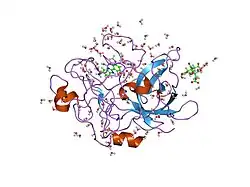

Structure

Urokinase is a 411-residue protein, consisting of three domains: the serine protease domain (consisting of residues 159–411), the kringle domain (consisting of residues 50-131), and the EGF-like domain (consisting of residues 1-49). The kringle domain and the serine protease domain are connected by an interdomain linker or connecting peptide (consisting of residues 132–158). Urokinase is synthesized as a zymogen form (prourokinase or single-chain urokinase), and is activated by proteolytic cleavage between Lys158 and Ile159. The two resulting chains are kept together by a disulfide bond between Cys148 and Cys279.[9]